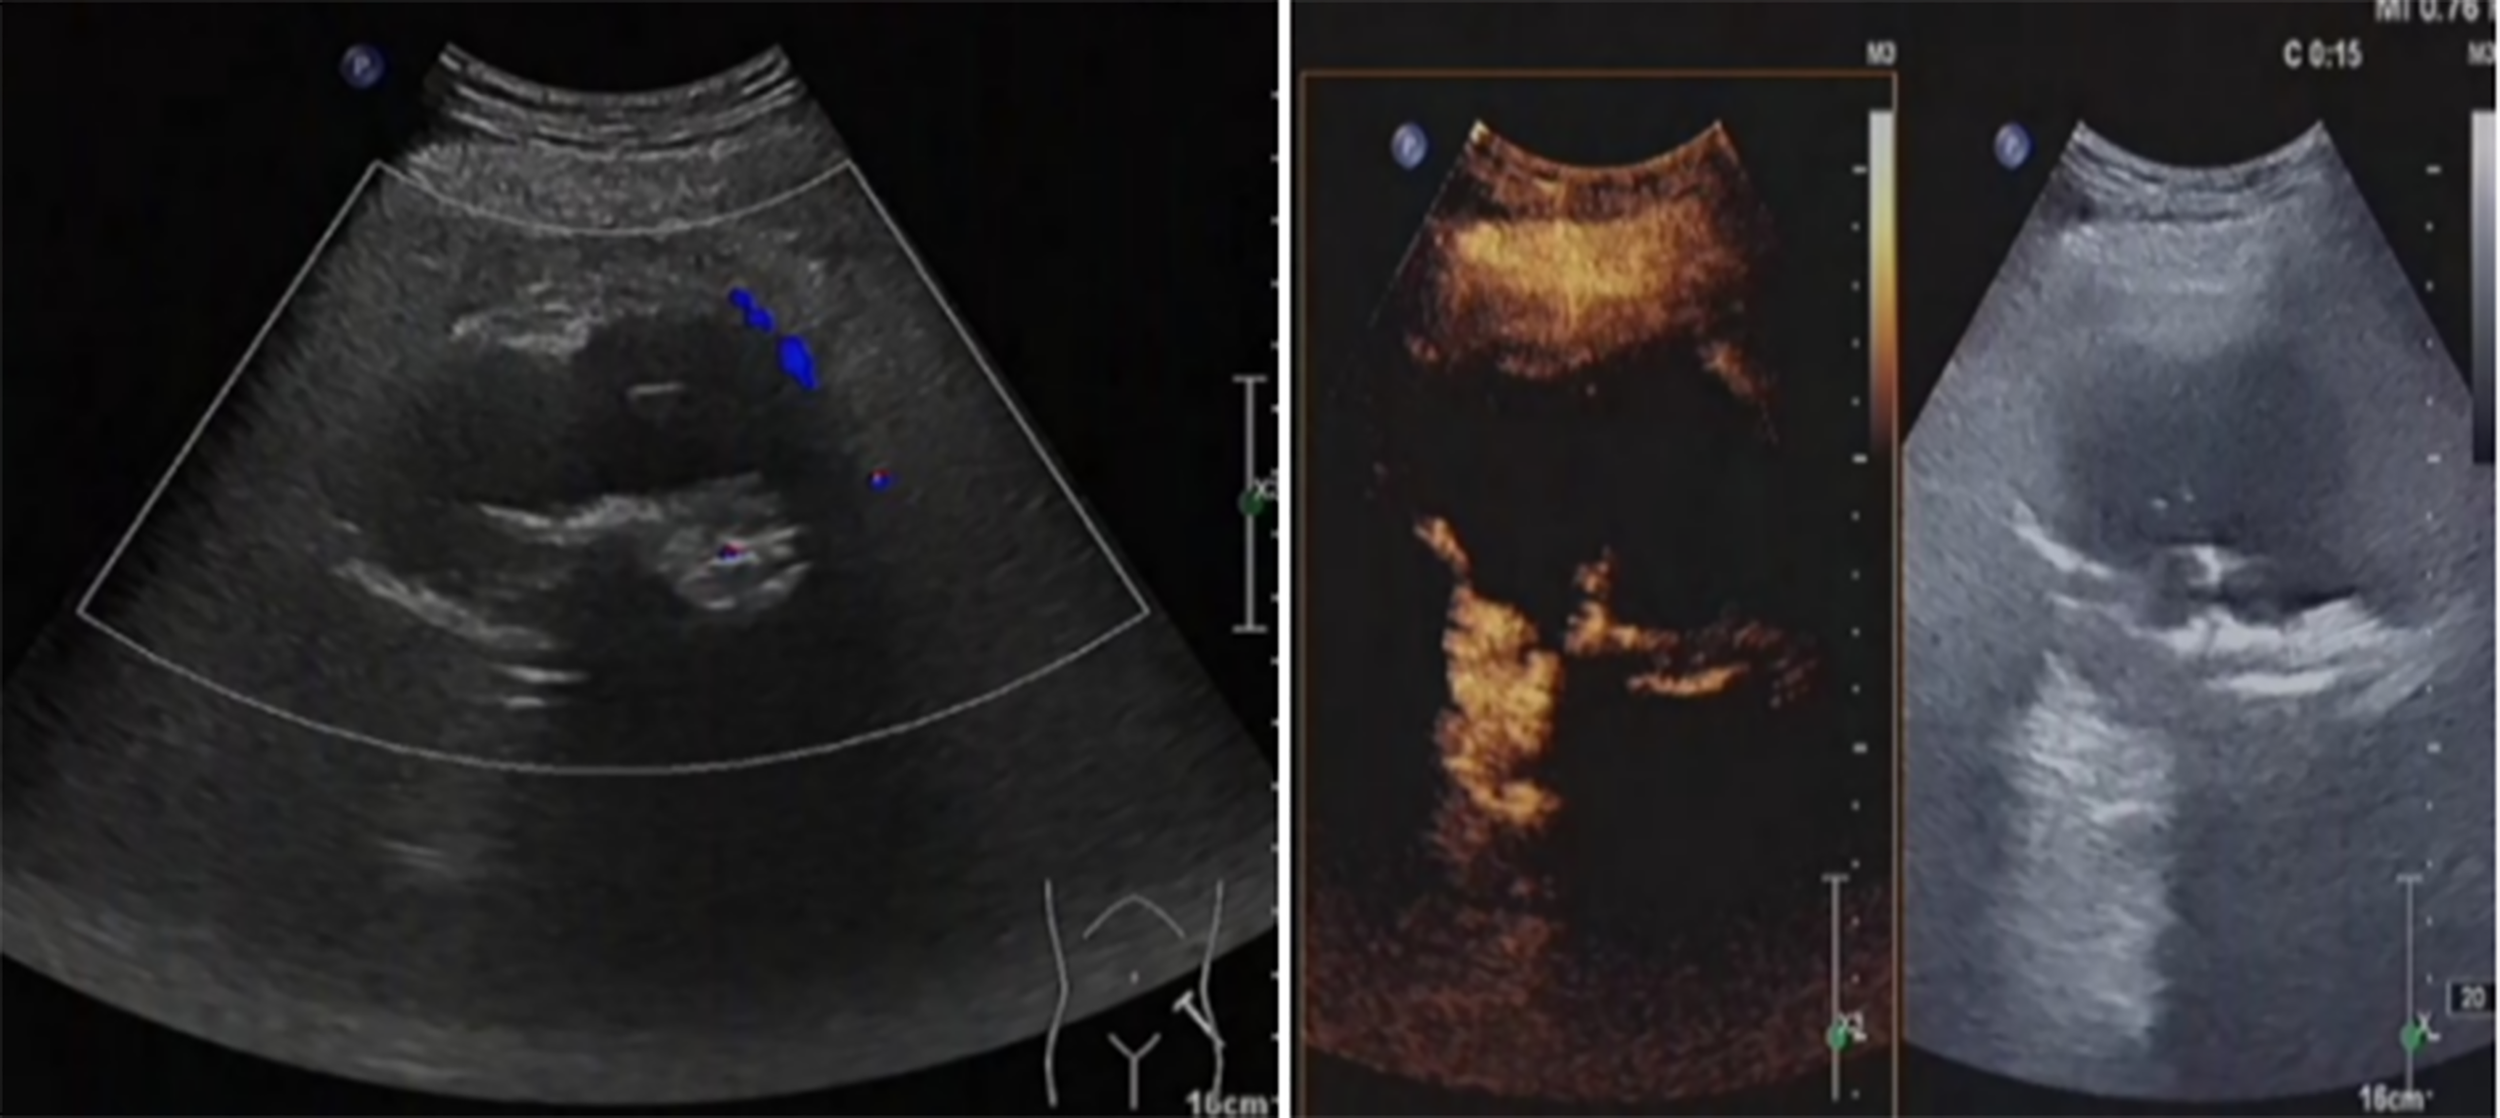

Figure 7

The hip tumor lesion was reduced compared with that before surgery, with a range of about 83mm × 54mm. No blood flow signal was observed in most areas, and the strip artery blood flow signal was observed in the medial margin, indicating no obvious activity in the lesion.